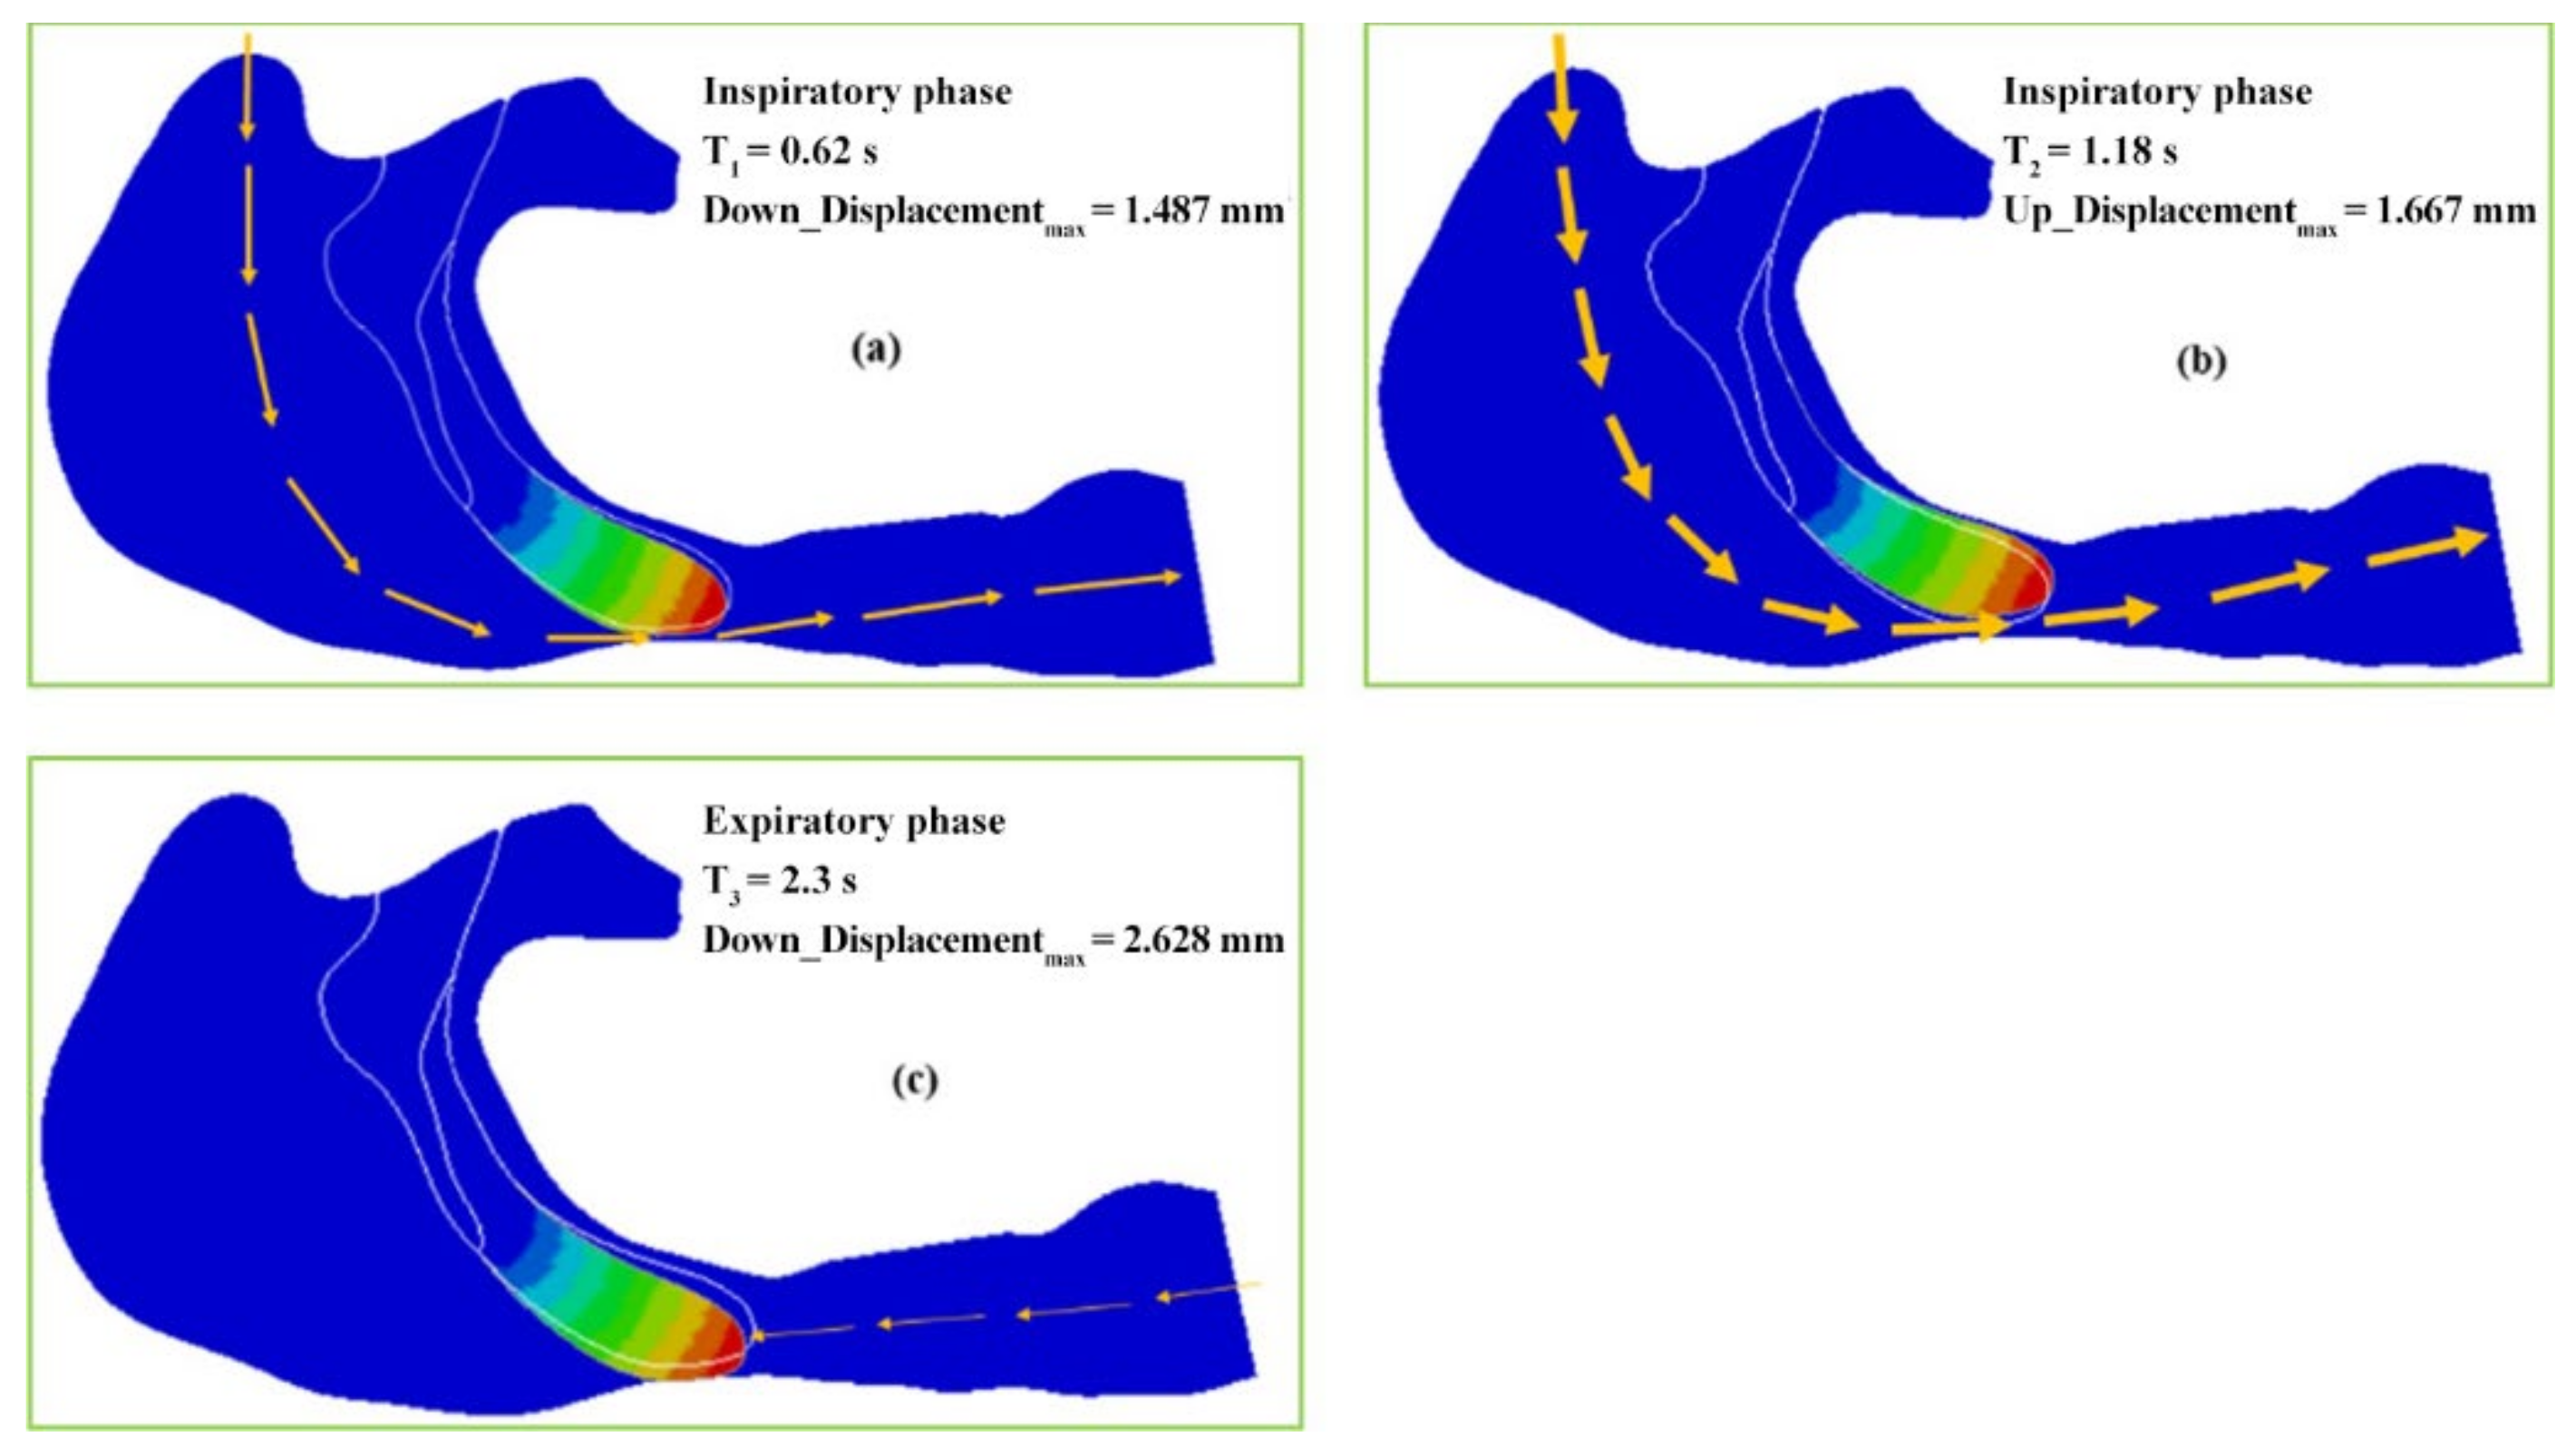

3.1. One-Way Valve Effect of Soft Palate

- The soft palate in pharyngeal cavity would exerts a one-way valve effect and collapses in the exhalation phase if the patient sleeps in the supine position, regardless of eupnea or apnea.

- The mechanical environment of the airway is directly dependent on the action of the airflow. If the mechanical properties of the soft palate remain unchanged, the pressure makes the soft palate collapse in apnea. In eupnea, the pressure allows the airflow to pass freely through the airway.